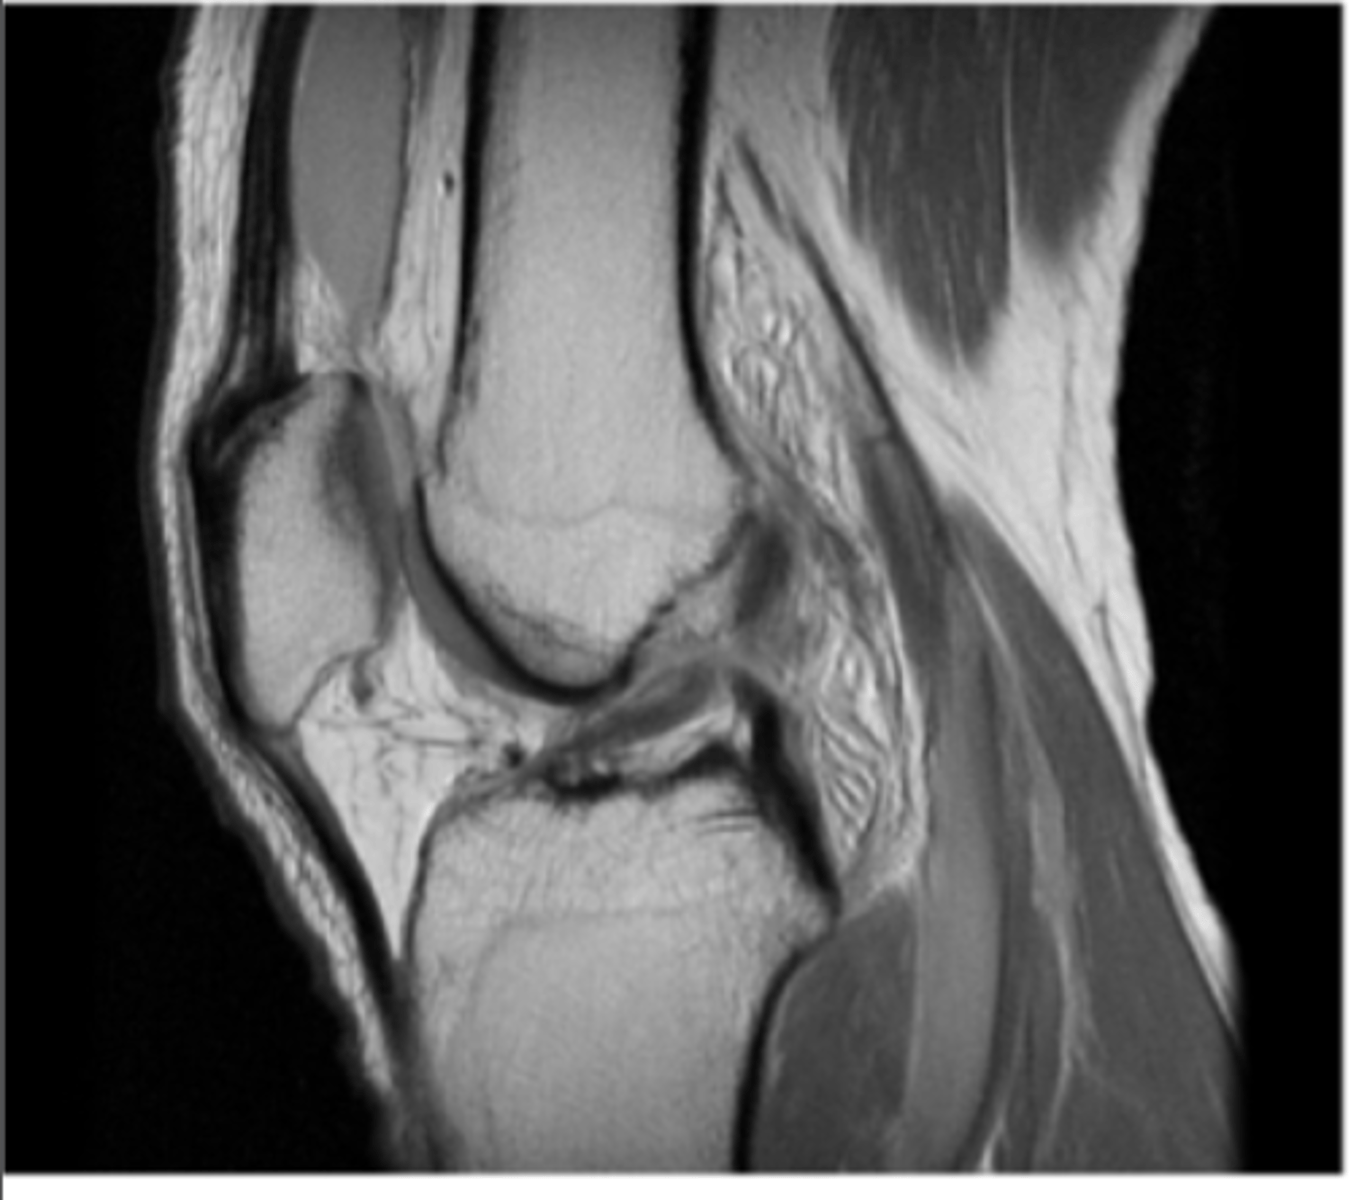

GOTCHA!! This is a NORMAL LCL!!

Define the pathology.